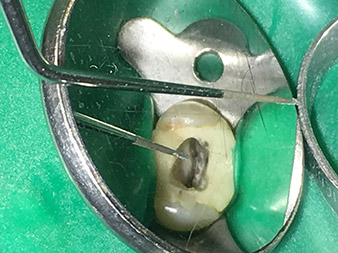

Traitement du canal radiculaire efficace et atraumatique

La conservation durable de la dentition est le principal objectif de l'endodontie moderne.

En plus du recours à des méthodes diagnostiques et thérapeutiques efficaces, l'utilisation des derniers outils et instruments techniques joue un rôle clé dans la réussite des soins aux patients. Le Dr Shahrad Nouraie Ashtiani et son équipe, qui exercent en cabinet à Brême, en Allemagne, traitent jusqu'à dix cas d'endodontie par semaine. L'aspiration des patients à un traitement le plus atraumatique possible associé à un bon pronostic de réussite constitue un défi quotidien pour le dentiste et interne en chirurgie orale qui a choisi l'endodontie comme spécialité.

Pour le Dr Nouraie Ashtiani, fervent utilisateur de la gamme élargie d'instruments W&H à ultrasons en endodontie, le traitement du canal radiculaire est non seulement plus efficace pour l'opérateur mais aussi moins astreignant pour le patient. L'expert en chirurgie dentaire maîtrise aisément même les situations les plus difficiles. Dans une interview récente, le spécialiste en endodontie nous a parlé des fonctions particulières qui caractérisent les instruments de W&H et a mentionné les risques possibles liés au traitement du canal radiculaire.

Illustrations : Dr Shahrad Nouraie Ashtiani, Brême